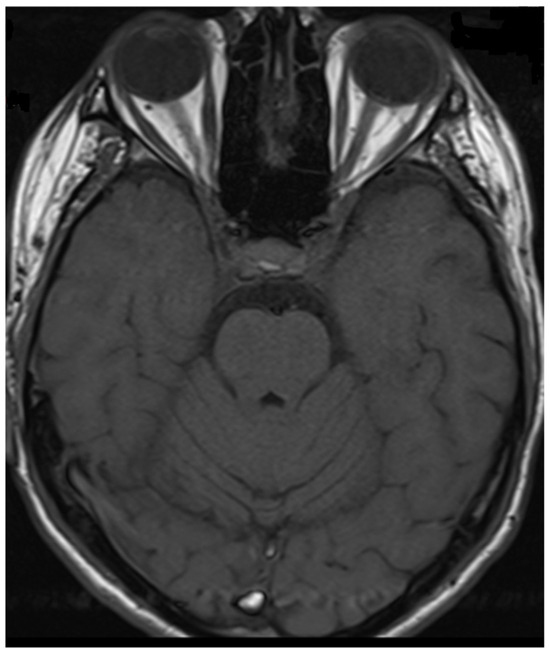

Figure 4.

Transverse FLAIR brain magnetic resonance image showing area of increased signal in the right middle cerebellar peduncle (December 2021).

During hospitalization in the neurology ward, Holter EEG was performed in which seizure episodes corresponded to changes in the recording. Interictal EEG showed rapid activity followed by slow theta waves and several sharp and slow wave complexes (Figure 1 and Figure 2). Topiramate was added to valproic acid at a target dose of 2 mg/kg of body weight. Gradual seizure relief was observed in the following weeks, and there were no other neurological manifestations for another nine months. After that time, in December 2021, the patient was admitted to the pediatric ward due to impaired consciousness and persistent vomiting, followed by paresis of the lower limbs. A brain MRI was performed, which showed “T2/FLAIR images reveal poorly defined areas of increased signal in the brain’s white matter, both above and below the tentorium, as well as in the periventricular and subcortical regions. These areas correspond to low signal regions in T1 images. The largest change area measures 19 × 14 mm and is located in the right middle cerebellar peduncle, which merges with changes observed in the pons. Additionally, there is a lesion in the right thalamus, measuring 10 × 24 mm, along with numerous scattered foci in the corona radiata and between the basal nuclei. Overall, the imaging findings primarily suggest acute disseminated encephalomyelitis (ADEM)” (Figure 3 and Figure 4). Cerebrospinal fluid examination revealed oligoclonal bands and an elevated protein level of 118.5 mg/dL (reference range: 15.0–45.0 mg/dL) and a slightly elevated leukocyte level of 29/mm3 (lymphocytes 72.4%, neutrophils 27.6%).

Considering the criteria mentioned above, we focused on two demyelinating syndromes for differential diagnosis: multiple sclerosis and neuromyelitis optica spectrum disorder (NMOSD). To accurately diagnose demyelinating lesions, we conducted tests to detect antibodies against aquaporin-4 (AQP4) and myelin oligodendrocyte glycoprotein (anti-MOG), following the established gold standard [9]. In addition to the positive/clear titer of anti-MOG antibodies and the exclusion of antibodies against AQP4, imaging tests—resonance imaging (MRI) of the head and spinal cord—help make the diagnosis. Unlike MS, magnetic resonance imaging of the brain reveals lesions with unclear boundaries, more often located subcortically, with a characteristic cloud-like shape and a particular location in the cerebellar peduncles [1,5,10,23]. MOGAD lesions are extensive, often bilateral, and located in the thalamus and basal ganglia [1,23]. In NMOSD, brain lesions are more often located near the third ventricle [5]; the involvement of the area postrema is particularly characteristic, and the lesions usually surround the lateral ventricles [5,6].